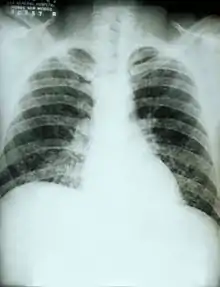

في حالة حدوث الإصابة بداء النوسجات، سوف تبدأ الأعراض بالظهور في غضون 3-17 أيام بعد التعرض للمسببات ويبلغ متوسط 12-14 يوما. معظم الأفراد المتضررين يكونون ذوي مظاهر صامتة دون ان تظهر أي آثار سيئة واضحة.[4] وتتميز المرحلة الحادة من داء النوسجات بأعراض غير محددة تصيب الجهاز التنفسي، وغالبا ما يكون مثل السعال أو الإنفلونزا. واظهرت نتائج تصوير الصدر بالاشعة السينية ان 40-70٪من الحالات كانت طبيعية،[4] لكن في الحالات المزمنة كانت تظهر كالسل؛.[5][6] يؤثر داء النوسجات على أكثر من جهاز معاَ من ما يجعله مميتاَ ان لم يتم معالجته.[7]